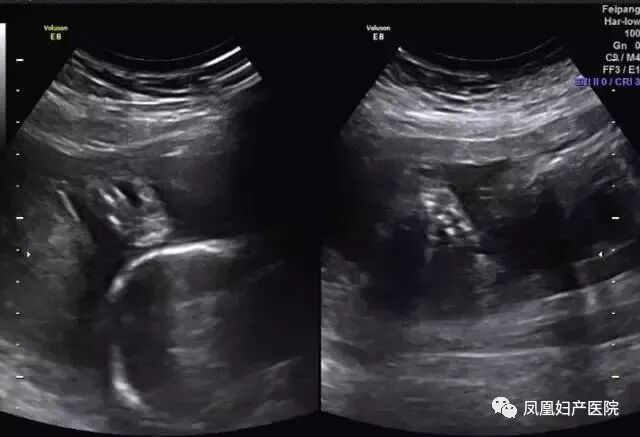

胎儿常见畸形检查图

(前脑无裂畸形,喙鼻)

(多发畸形)